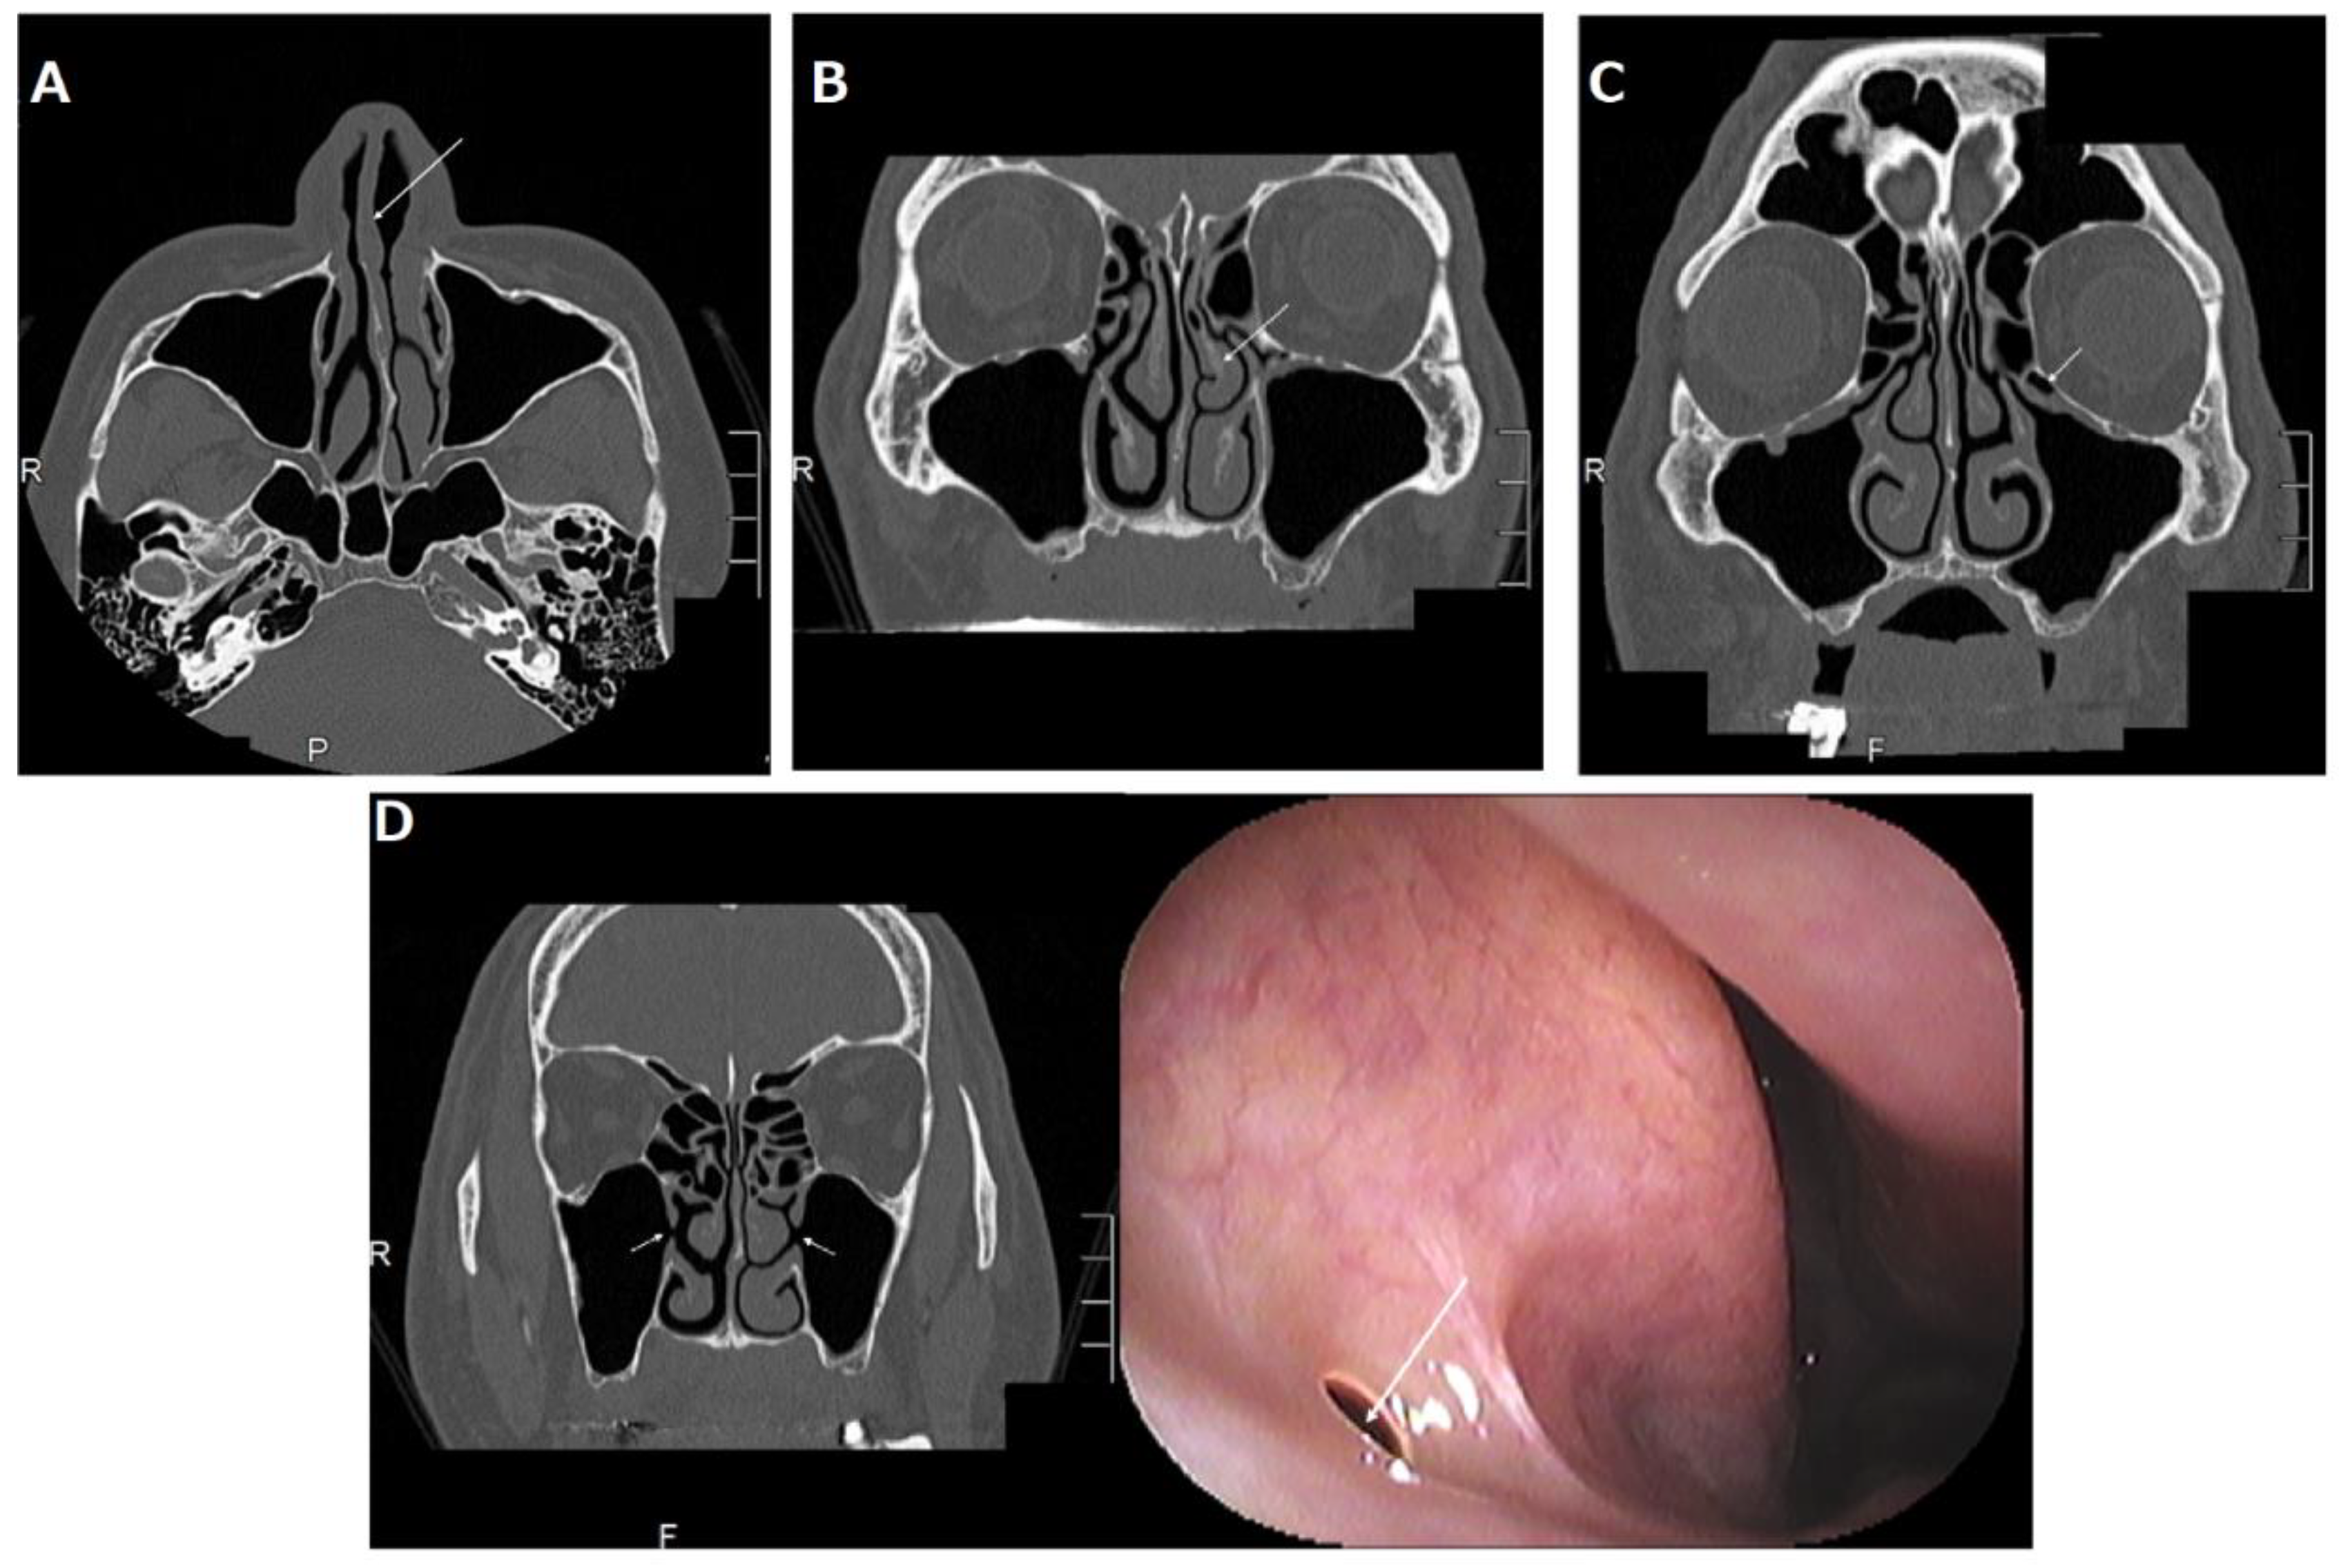

2.3.1. Deviated Nasal Septum

2.3.2. Concha Bullosa or Paradoxical Middle Turbinate

2.3.3. Haller Cells

2.3.4. Accessory Ostium